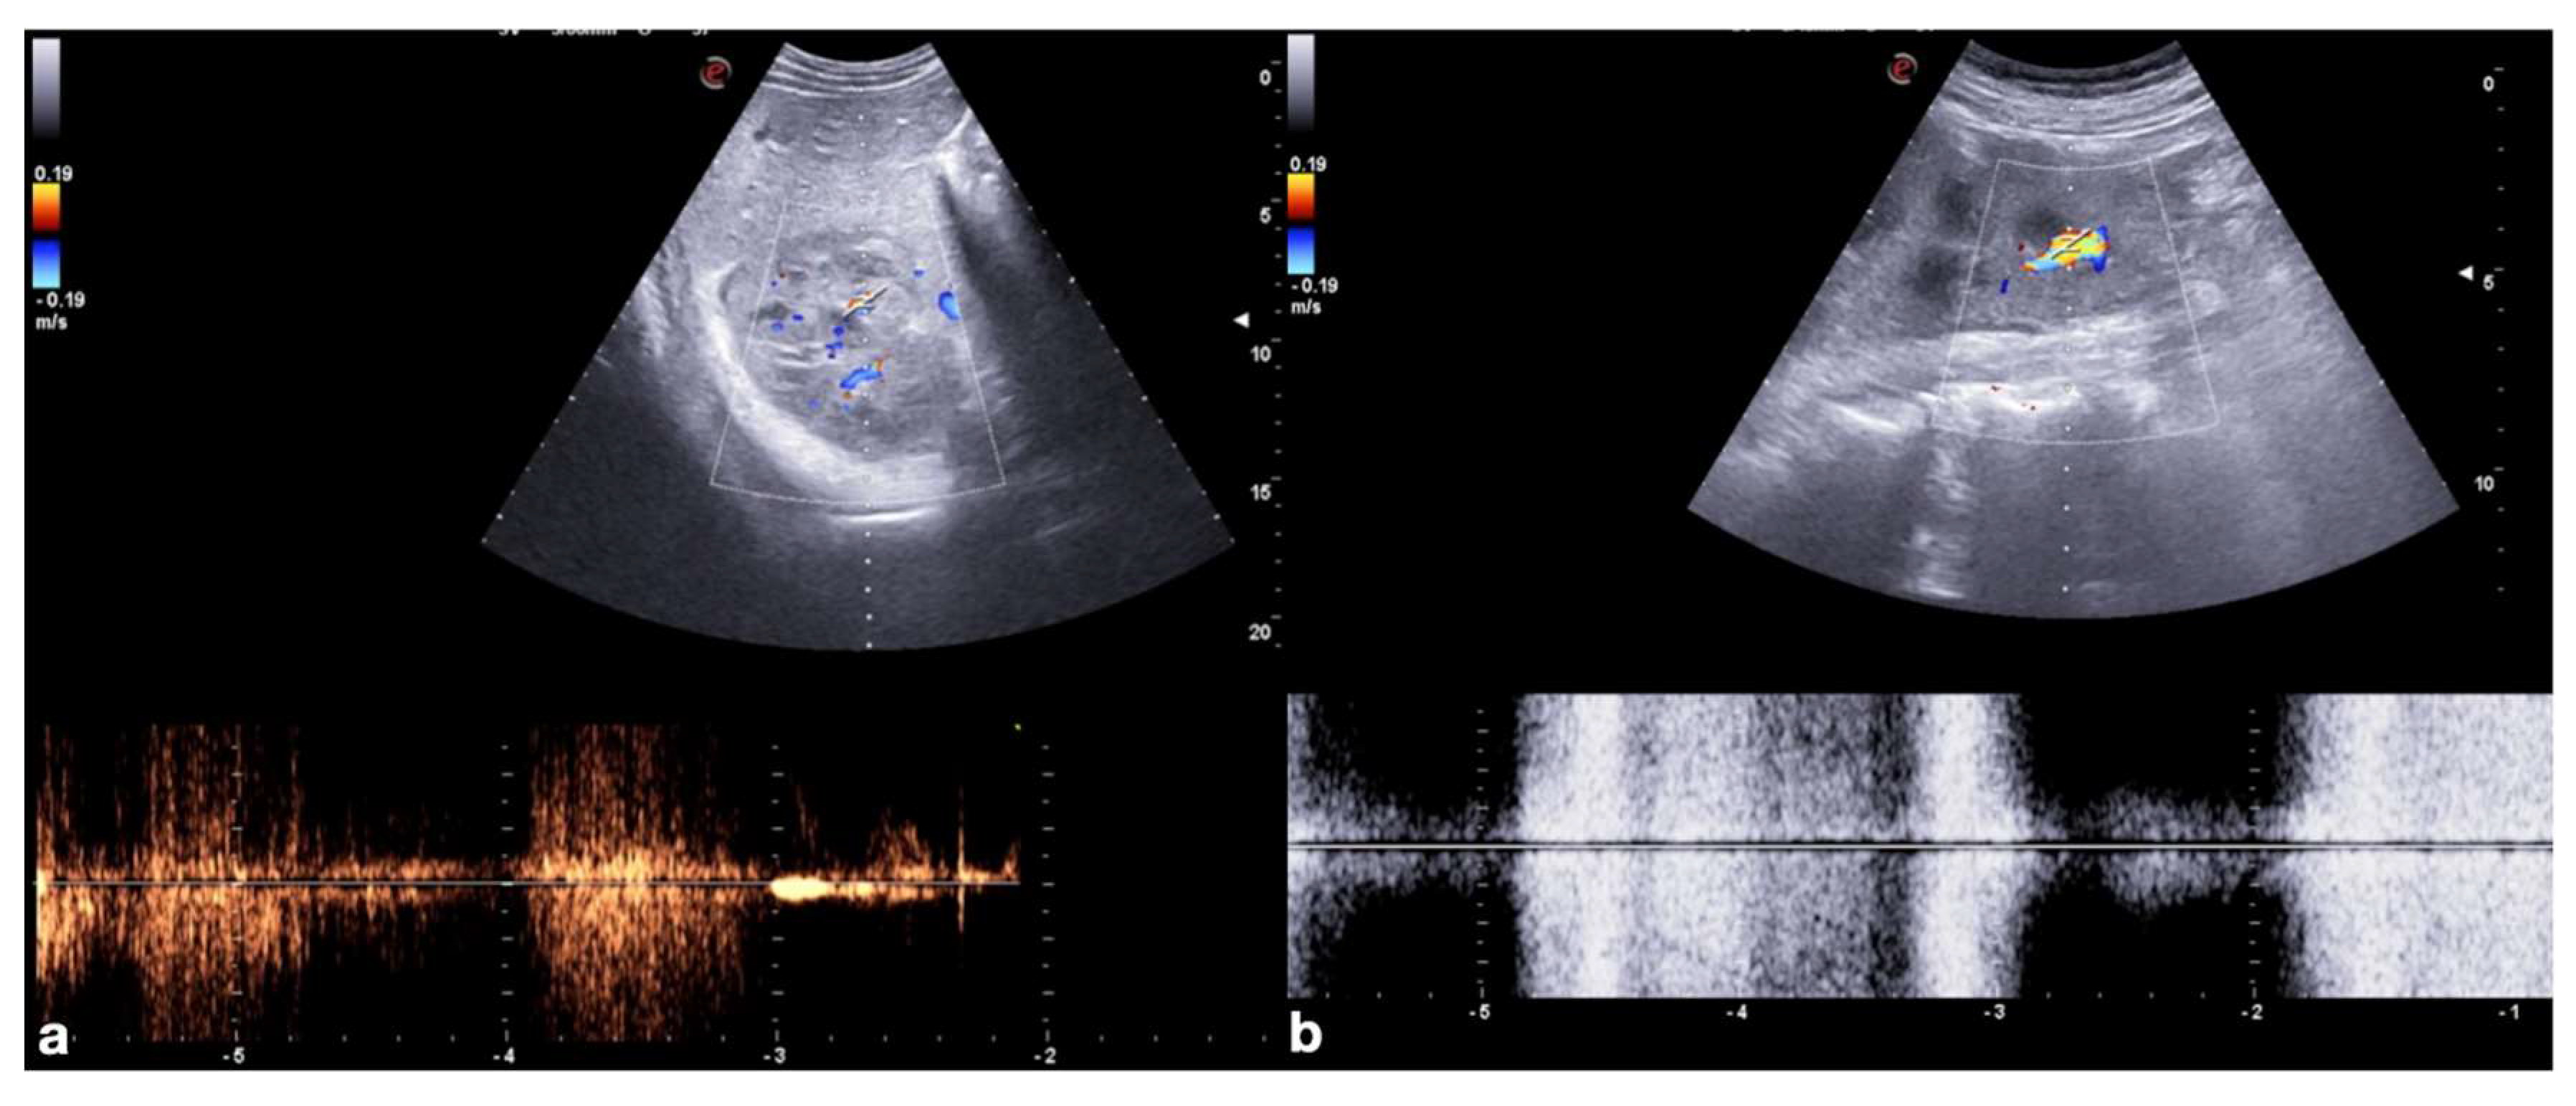

2.3.2. Vascular Injuries

- Active bleeding:

- Contained vascular injuries: